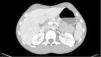

Fifteen-year-old male with blunt abdominal trauma. He presents to the ER at 12h with diffuse abdominal pain unresponsive to the usual analgesic medication. He shows a good state of health; vital signs look good; and the blood tests conducted confirm levels of amylase of 3005U/l (20–100U/l). An abdominal ultrasound scan is conducted that shows the presence of abundant free fluid in the pouch of Douglas which leads to conducting an additional abdominal CT scan with contrast that shows the complete rupture of the pancreatic body (Fig. 1). Initially, the management of the patient is conservative under intensive monitoring at the ICU. A magnetic resonance imaging confirms the aforementioned complete rupture (Fig. 2). Yet despite this fact, conservative management is not withdrawn given the patient's complete and constant stability. After seven (7) days, the progression of the rupture is favorable according to the ultrasound scan and free fluid is completely gone. The patient is discharged from the hospital after eight (8) days with no symptoms or any associated complications.